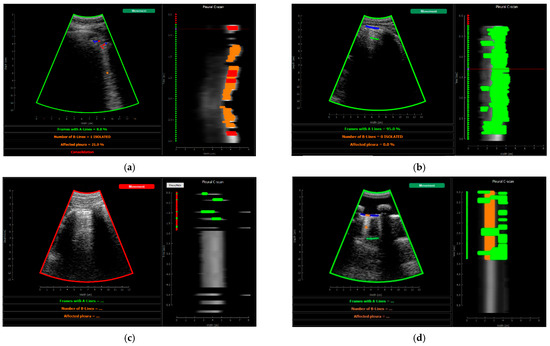

2.5.4. Visualization

3.2. Real-Time Implementation Results